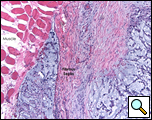

Eleven months later, he presented with a several month history of a painful fixed, firm mass over the pectoral area of the left chest and a smaller mass inferior to this (Figure 1). CT scan demonstrated a new 2 cm nodule in the left upper lobe associated with an anterior chest wall mass six centimeters in size in addition to bilateral new pulmonary nodules (Figure 2). The mass was tethered to the skin and in danger of eroding through it. The patient underwent en-bloc resection of the chest wall and adjacent lung (Figures 3a-c). The resulting defect (Figure 4a) was reconstructed with 2 mm Gore-Tex patch (Figure 4b) and pectoralis major muscle flap (Figure 4c) with primary skin closure (Figure 4d). The pathology revealed metastatic chordoma (Figures 5a-d). The patient recovered well, leaving the hospital on the sixth postoperative day.